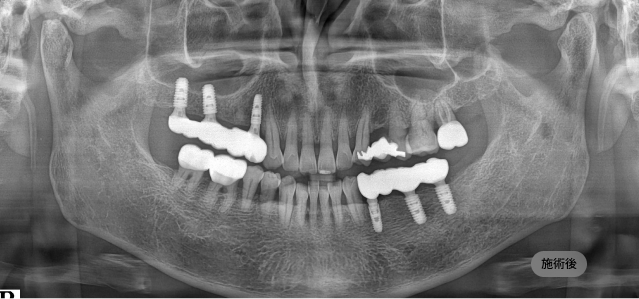

画面をドラッグして前/後を比較してみてください